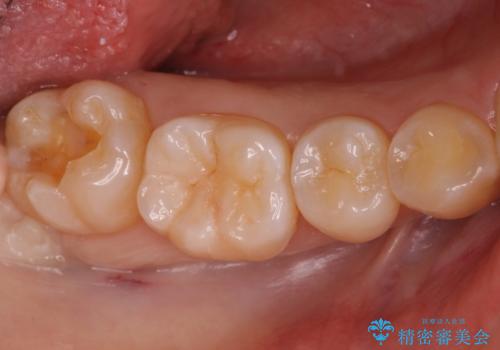

奥歯の深い黒ずみ セラミックインレーでの治療

- 奥歯の溝の黒ずみが気になるとのことで来院されました。

変色しない材料をご希望されたためセラミックインレーでの治療となりました。

- 右下7 セラミックインレー 77,000円費用は治療当時の料金となります